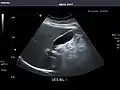

Aorta

Aorta: Visualized portions normal in caliber, 16 x 15 mm.